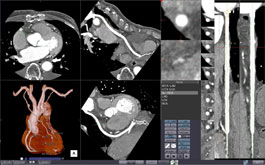

CT CORONARY ANALYSIS

With contrasted CT images, this protocol automatically extracts the coronary arteries and displays the results in views such as MIP, CPR, and Straight CPR. Calculation of vessel stenosis is available.